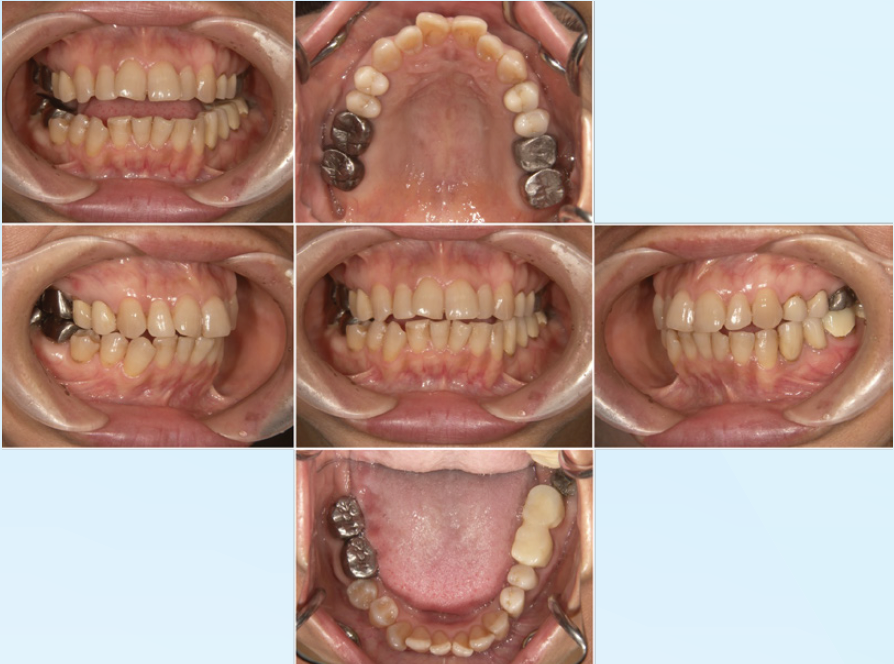

<緊急処置後、初期治療前の口腔内写真と14枚法>

歯周病の程度は軽度。前歯部開口咬合状態を呈し、

既往歴はほぼ臼歯部に集中している

口腔内の傾向から臼歯に過度な負担があり、

さまざまな病態に至っていると推測する

(図19-1)

(図19-2)

<臼歯部の感染根管治療終了後の14枚法>

(図20)

術前には数歯に根尖病変を疑う透過像が確認できたが

術後改善傾向にあることが確認できる